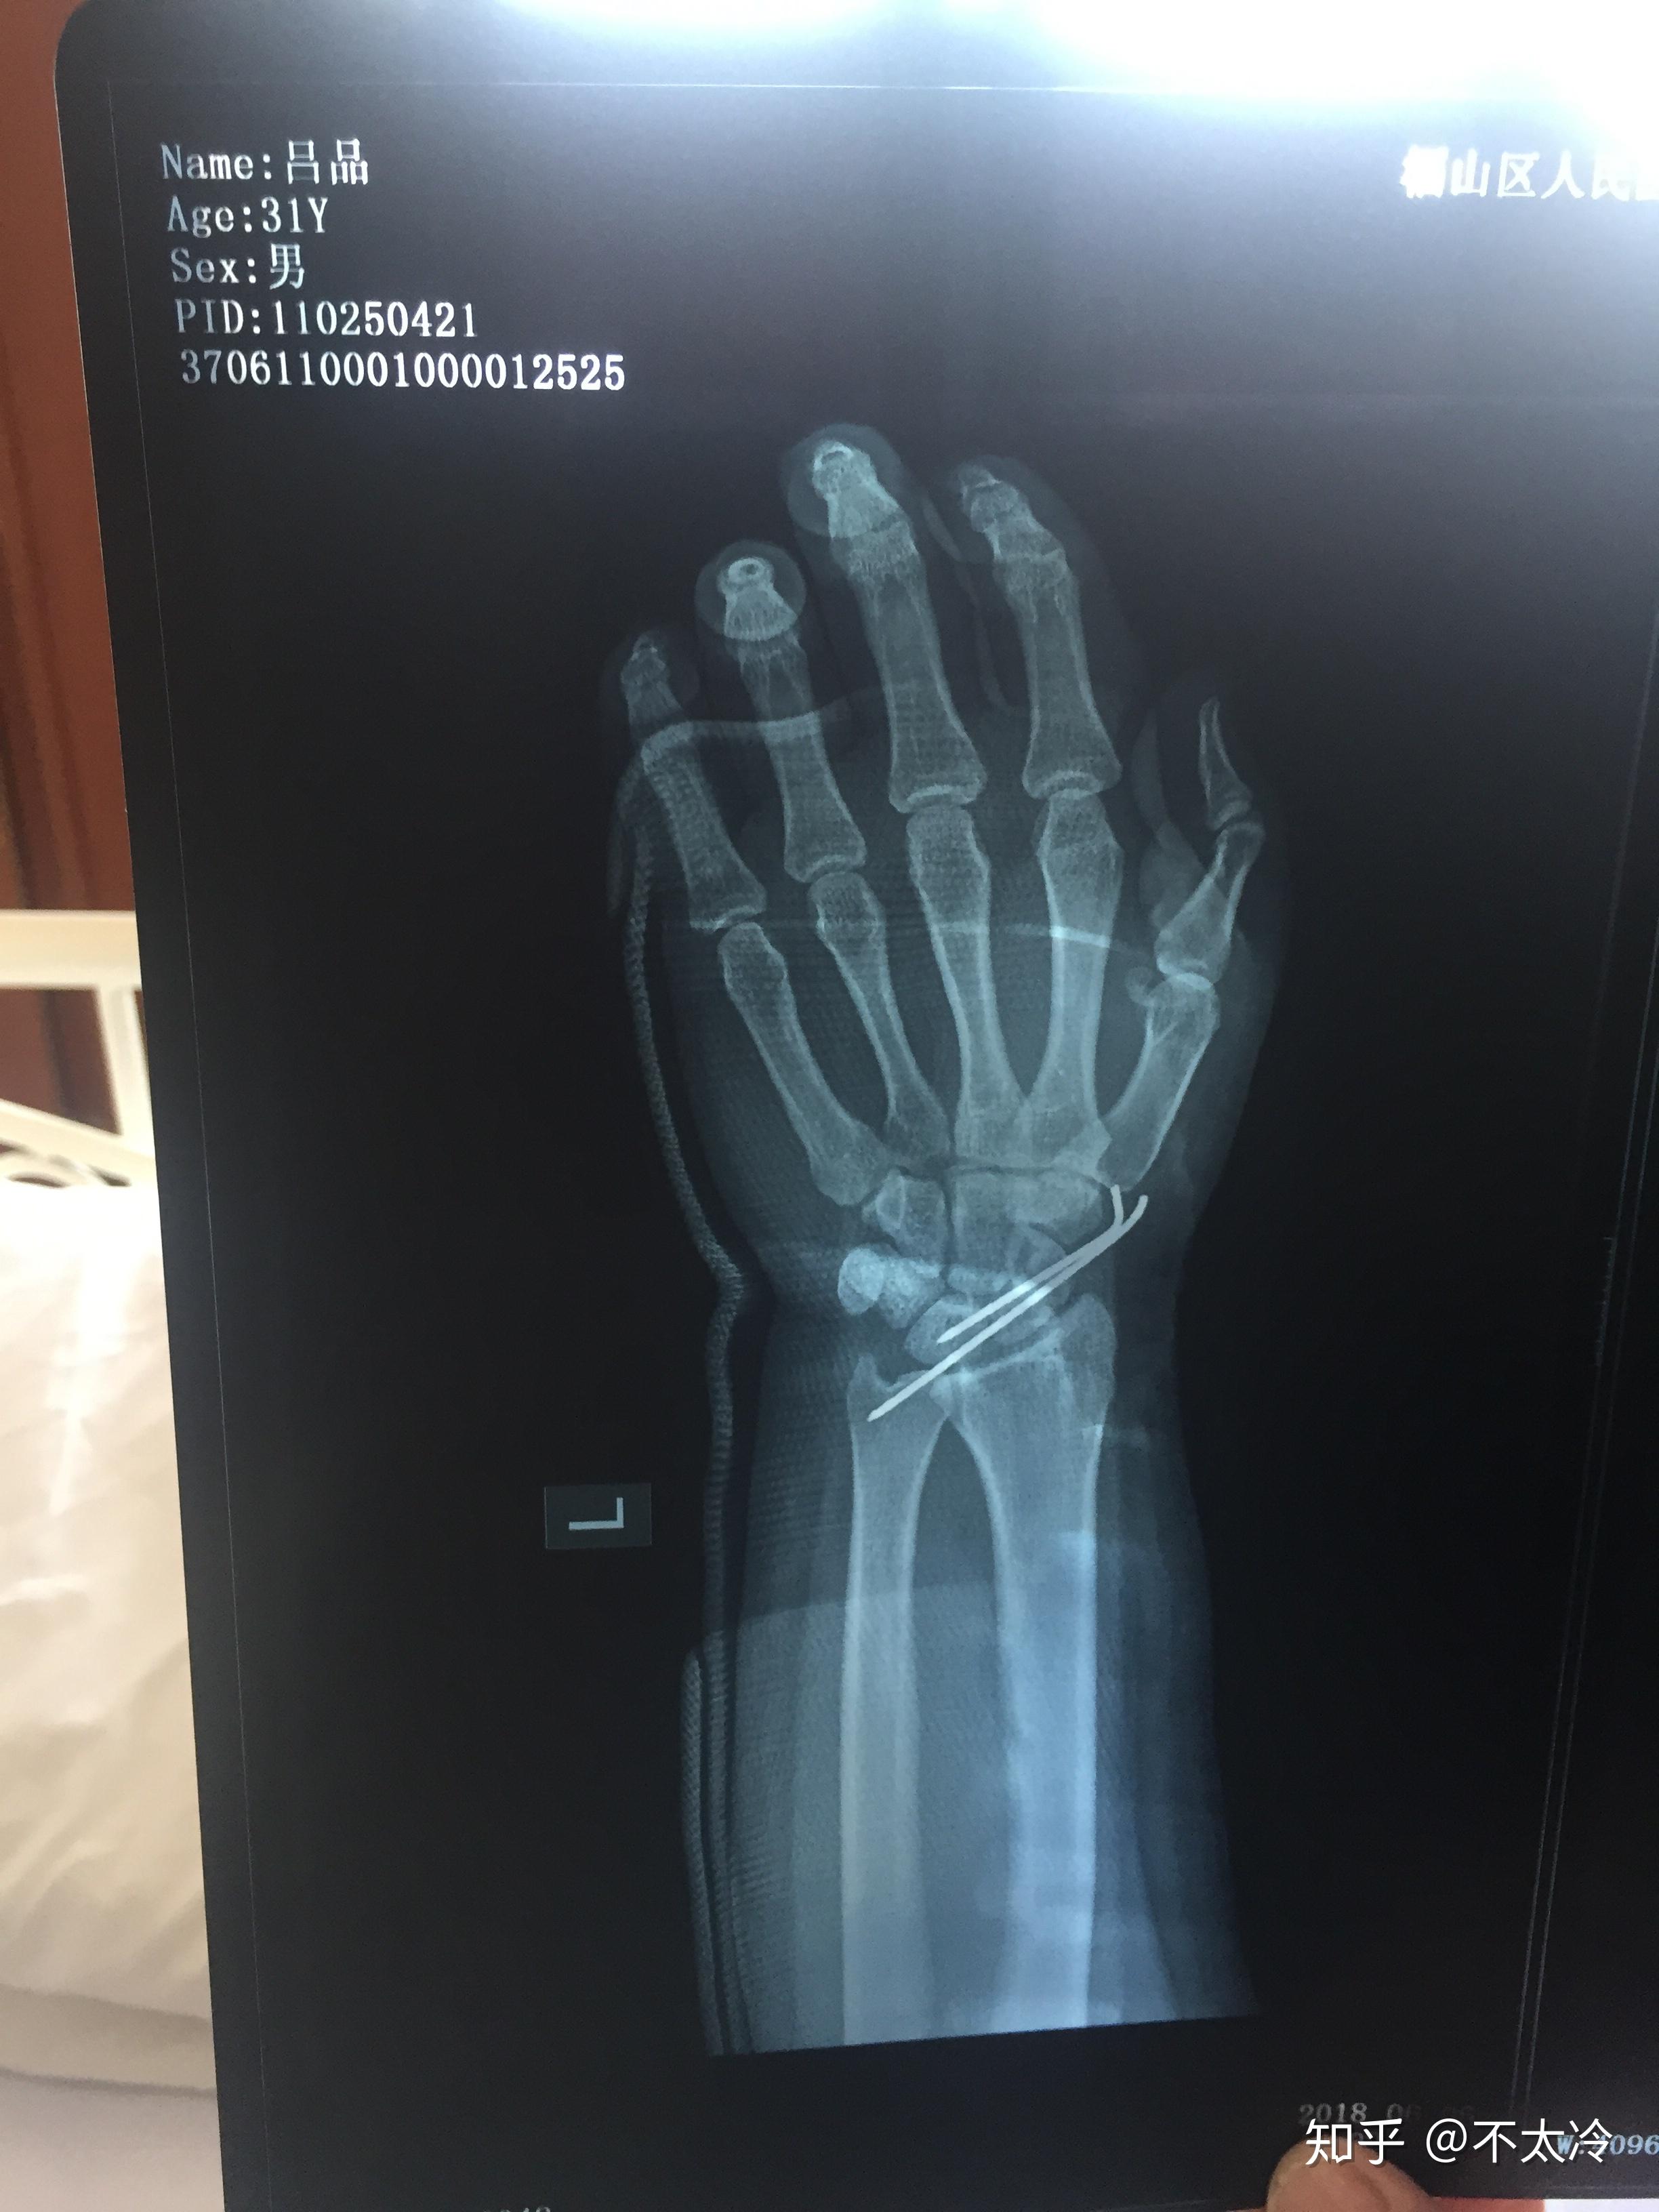

我左腕舟骨骨折,做手术穿了钢钉,有木有医学达人告诉我我可以喝酒吗?

图片尺寸2448x3264